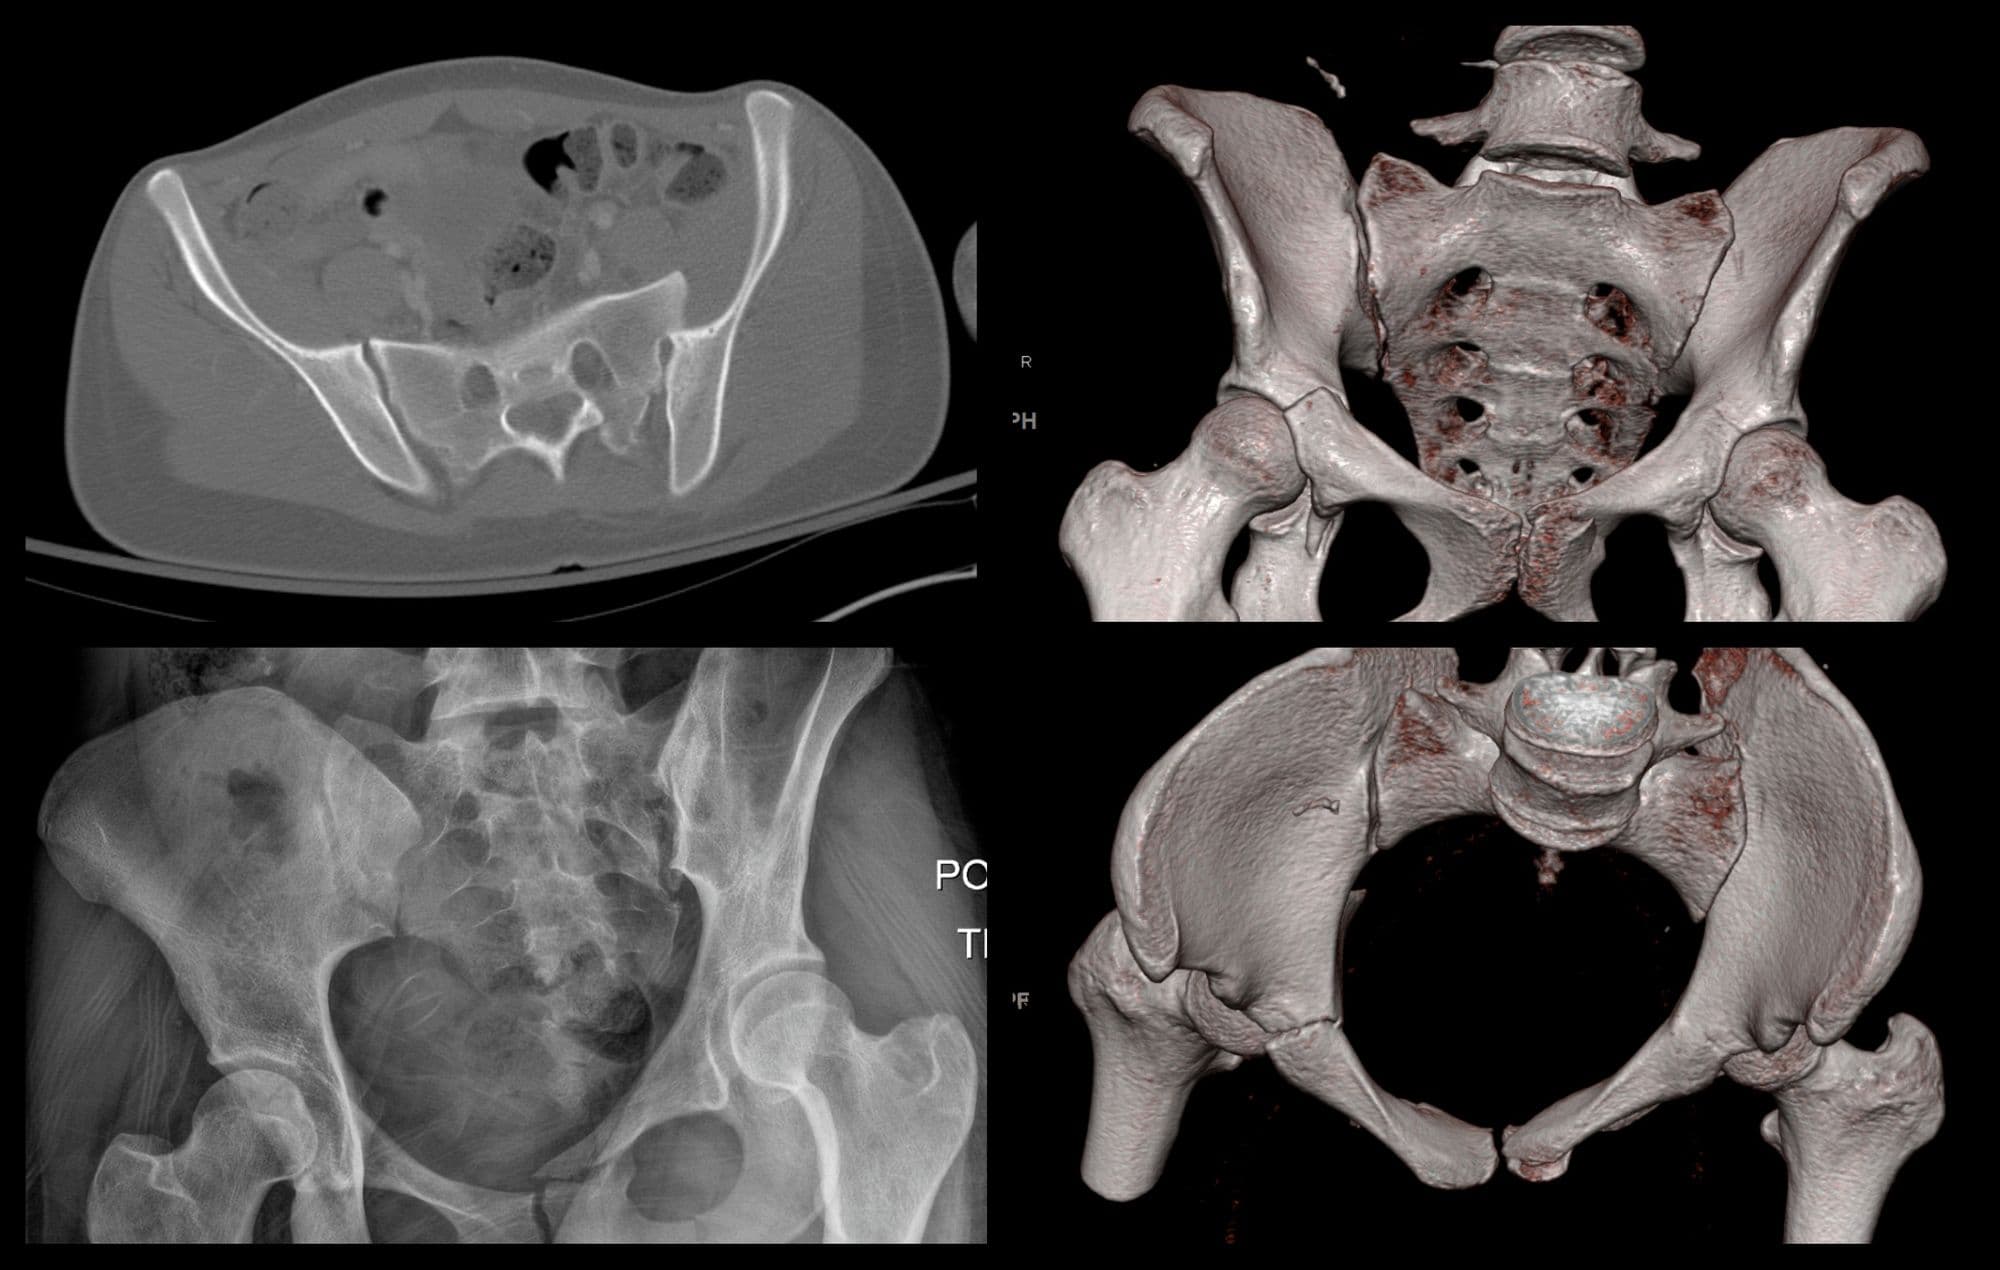

Posterior Wall Acetabulum ORIF